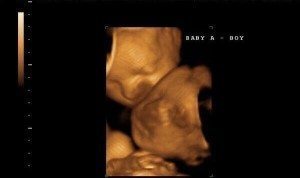

I thought I was having a miscarriage due to some bleeding. We went to get checked at my doctor (I was 9 weeks). I prayed the whole way and couldn’t look at the screen when she did the ultrasound. She asked my husband, “Do you see what I see?” He sighed and smiled and said, “A baby…” She said, “I see 2…” I told my husband I prayed so hard God gave us another one! Emotions went from one extreme to the other…

We found out our previous pregnancy wasn’t viable at our 8 week ultrasound. So going into this ultrasound (also at 8 weeks), so soon after, I was completely detached. And he was scared. So we got on the table and she started. She goes, “Ah, there’s the heartbeat. And here’s the other one.” And my husband just went, “The other what?” She replies, “Heartbeat.” And he still didn’t catch on. I turned my head and said, “There are 2 babies.” And then it went crazy from there. They are 15 months now.

The ultrasound tech told my husband to sit down….she told us there were 2 and the room immediately started spinning. My 2 daughters, who were with us, started listing off all the things we were going to have to buy. The tech just kept laughing!

The tech asked “do twins run in your family?” I said “Yes, rampant.” She said, “Well guess what?” My husband screeched,”WHAT?!”

I had an ultrasound at 11 weeks due to bleeding. I was told it was either a miscarriage or torn placenta. The tech said, “Here’s a heartbeat…and here’s the second heartbeat.” I admit it took me a second to catch on, but a full 10 minutes later my husband said, “Wait, are you saying there’s two babies??”

We did IVF and the afternoon before our 6-week ultrasound I started bleeding. I already had 1 early miscarriage so I thought the worst. The next morning we went in for the ultrasound and our infertility doctor came in the room and took out “the wand” and started. I held my breath and prayed. He said, “OK, so I’m seeing 3 sacs… which means triplets…” I looked at my husband and I’ve never seen him so scared in his entire life!!! Then in the next breath our doctor said, “Wait a minute — no, that one is a blood clot, which explains the bleeding. So you’re having twins!” I looked back at my husband and you’d think he was just found not guilty of murder! He was so relieved! And so was I. Twins we were mentally prepared for. I burst into tears and laughter and he looked like he was about to pass out. It was a great moment; finally getting our babies!!!